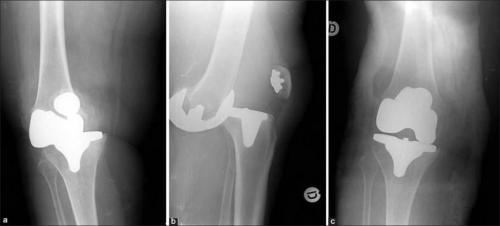

Такое может случиться, если очень торопиться. Это вывих коленного импланта.

Если позиционирование протеза выполнено неправильно, рано или поздно пациенту диагностируют вывих или деформацию, значит, вести привычный образ жизни он все равно не сможет. Если элементы протеза недостаточно зафиксированы – он становится нестабильным. Возникает боль во время движений. Результат операции оставляет желать лучшего.